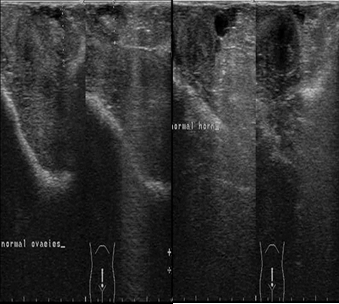

The ultrasonographic imaging of the uterus and ovaries was performed daily 9th day postpartum then followed by examination twice weekly until the 21st day postpartum. The ultrasound examination showed normal uterine involution and no abnormal secretions in the uterus (Figure 2).

Figure 2.Ultrasonographic image of ovaries (a) and uterine horn (b) at the 9th day postpartum in female camels, the image illustrate normal ovarian structure with no ovarian cysts and the uterus showed normal uterine involution and no abnormal discharges.

The serum progesterone level decreased sharply after parturition during the 1st, 3rd and 9th days postpartum, which is considered physiological decrease due to the lysis of corpus luteum of pregnancy and the drop of placenta which is considered another source of progesterone to maintain pregnancy, in addition the lactation status significantly affects on serum progesterone level16. It was proved that the plasma concentration of progesterone was increased by the 5th days after mating and remained high throughout most of pregnancy, and it starts to decline by the 2nd weeks before parturition3, 17. In addition, the low level of progesterone detected in the 1st day postpartum concur with previous studies during postpartum females in camels18 and other species19. Similar changes in the hormonal levels were observed during pregnancy, parturition and postpartum in llama20, 21. The ultrasonographic examination was performed twice weekly during the postpartum period starting from the 3rd day postpartum until the 21st day postpartum, there was normal uterine involution and no abnormal secretions in the uterus, this was in agreement with previous studies by Abu-Seida22, Derar, Ali23, who found that the uterine involution was completed in female camels from 25th until 30th days postpartum.